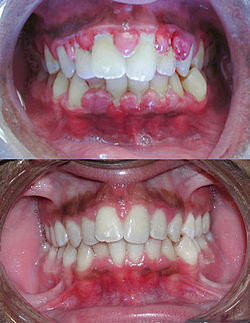

Гингивит: фото до и после

Если был диагностирован острый гингивит, все неприятные ощущения в области десен должны исчезнуть. После лечения хронического гингивита десны возвращаются к нормальной величине и перестают кровоточить, пародонтальные карманы исчезают. При грамотном лечении и удовлетворительной гигиене рецидивы заболевания отсутствуют в течение нескольких лет.